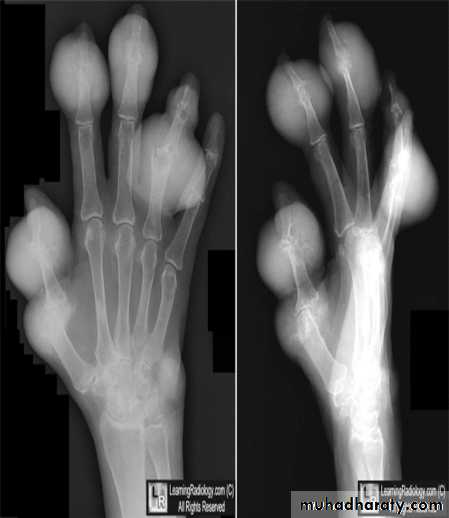

GOUT

Heterogeneous group of entities characterized by recurrent attacks of arthritis secondary to deposition of sodium urate crystals in and around joints.

Radiographic features:

Lower extremity > upper extremity; small joints > large joints

* First MTP is most common site

* Marginal, peri articular erosions: overhanging edge

* Erosions may have sclerotic borders

* Joint space is preserved

* Soft tissue and bursa deposition

Tophi: juxtaarticular, helix of ear

Bursitis: olecranon, prepatellar

* Erosions and tophi only seen in longstanding disease

* Tophi calcification, 50%

*Chondrocalcinosis